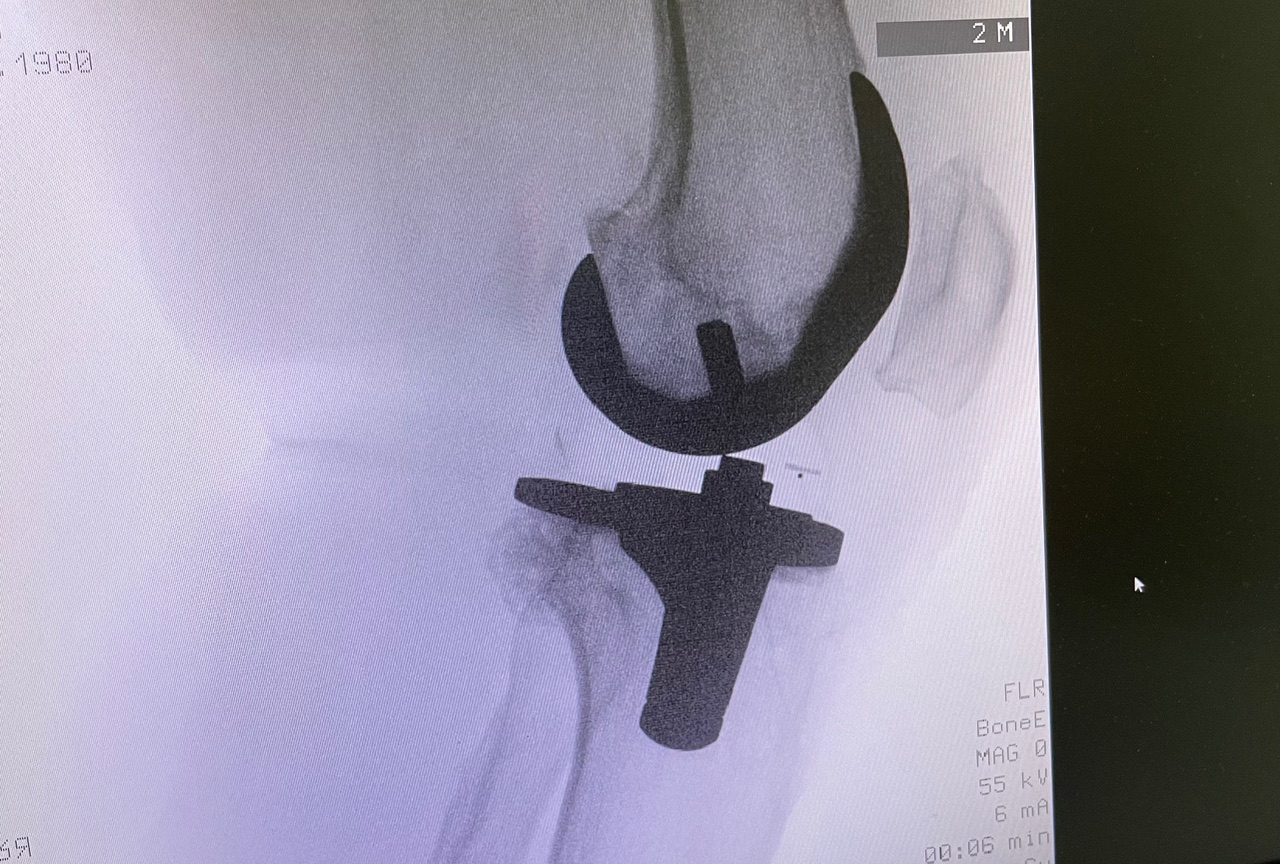

Η ολική αρθροπλαστική γόνατος είναι χειρουργική επέμβαση κατά την οποία αντικαθίσταται η φθαρμένη άρθρωση του γόνατος με τεχνητά εμφυτεύματα.

Στόχος είναι η ανακούφιση από τον πόνο, η βελτίωση της κίνησης και η αποκατάσταση της λειτουργικότητας του γόνατος.

Κατά την ολική αρθροπλαστική:

• αφαιρούνται οι φθαρμένες αρθρικές επιφάνειες

• τοποθετούνται μεταλλικά εμφυτεύματα στο μηριαίο οστό και την κνήμη

• παρεμβάλλεται ειδικό ένθετο πολυαιθυλενίου

• σε επιλεγμένες περιπτώσεις αντικαθίσταται και η επιγονατίδα

Στόχος είναι η σωστή ευθυγράμμιση, η σταθερότητα και το φυσικό εύρος κίνησης.